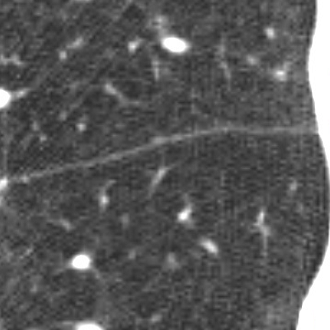

We applied the described segmentation pipeline to the 14 testing datasets which were not used for training and validation. Segmentation including postprocessing takes less than 6 seconds for a case. We compared our method to two other approaches: 1. a non-deep-learning-based automatic method [Lassen et al.(2013)Lassen, van Rikxoort, Schmidt, Kerkstra, van Ginneken, and Kuhnigk] 2. the same u-net as proposed but without weighting. The mean distance from the visible fissure improved to 1.46 mm (without weighting: 2.08 mm). See Figure 2 for plots and Figure 3 for screenshots.

We trained a 3D u-net for a lung lobe segmentation task and showed that emphasizing the lobar boundaries in the loss function improved the segmentation results (see Figure 2 and 3). The segmentation quality is comparable to the method proposed in [Lassen et al.(2013)Lassen, van Rikxoort, Schmidt, Kerkstra, van Ginneken, and Kuhnigk] and even slightly better for the left lobes. This study was performed on a small amount of data. In future work, we plan to train with the same architecture on a much larger database including a wide range of pathologies and performing an extensive evaluation with participation in the LOLA11 [LOLA11()] challenge.